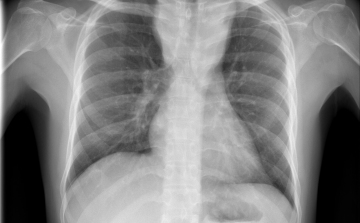

Már a 26. tüdőátültetést végezték el Magyarországon

A 26. tüdőátültetést végezték el Magyarországon a közelmúltban - közölte az Országos Onkológiai Intézet és a Semmelweis Egyetem hétfőn az MTI-vel.